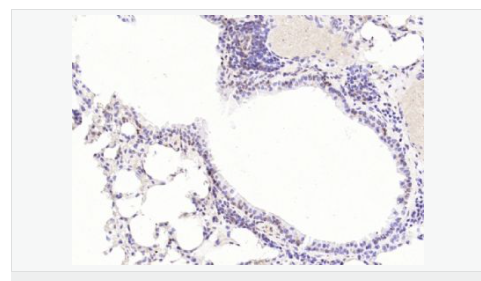

| 產(chǎn)品應(yīng)用 | WB=1:1000-2000 ELISA=1:1000-5000 IHC-P=1:100-500 IHC-F=1:100-500 Flow-Cyt=1ug/Test ICC=1:100-500 IF=1:100-500 (石蠟切片需做抗原修復) not yet tested in other applications. optimal dilutions/concentrations should be determined by the end user. |

| 細胞定位 | 細胞核 細胞漿 |